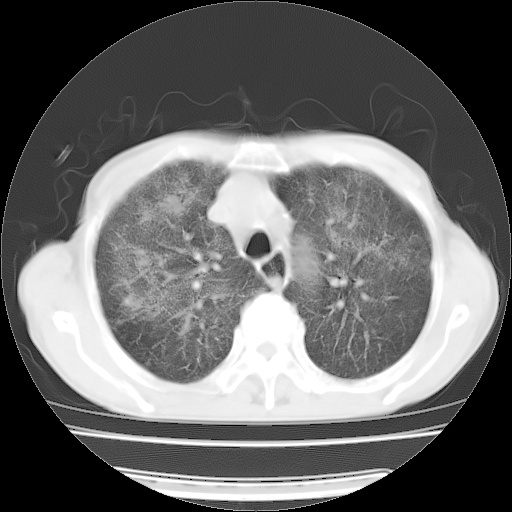

病人发热、气促就诊。原二周前已行ct扫描,当时诊断为双肺下叶、右肺中叶支气管扩张并感染,双肺上叶片状渗出性病变。今天复查胸部ct,双肺下叶支气管扩张并感染病灶较前明显吸收,但双肺上叶渗出性病变较范围较前明显增大。

双肺多发大片状、斑片状高密度渗出影,部分实变,考虑病毒性肺炎。